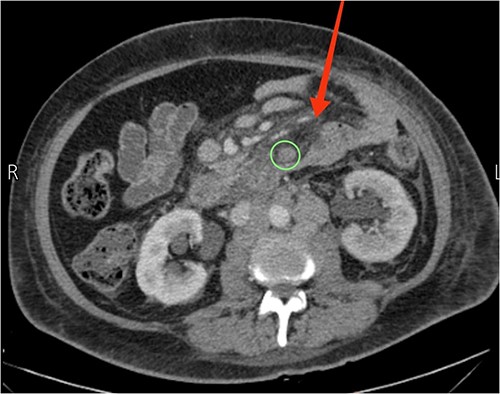

A 57-year-old female presented to our emergency department with diffuse abdominal pain, distention, constipation, nausea, and back pain of one-month duration, accompanied by a 19.8 lbs (9 kg) weight loss. Three months earlier, the patient sought care at another hospital for recurrent abdominal pain. Computed tomography (CT) scans revealed suspiciously enlarged lymph nodes in the peripancreatic and para-aortic regions, notably a 4.1 × 2.4 cm necrotic and heterogeneous node in the para-aortic area (Fig. 1). Subsequent ultrasound-guided fine needle aspiration and fine needle biopsy confirmed a metastatic poorly differentiated adenocarcinoma and an acellular smear, respectively. Upper and lower endoscopic studies showed unremarkable findings. The diagnosis of CUP origin was made.

Axial view CT scan showing the head of the pancreas (P), enlarged peripancreatic lymph nodes (the two arrows at the top), and a 4.1 × 2.4 cm necrotic and heterogeneous enlarged lymph node in the para-aortic area (the arrow at the bottom).